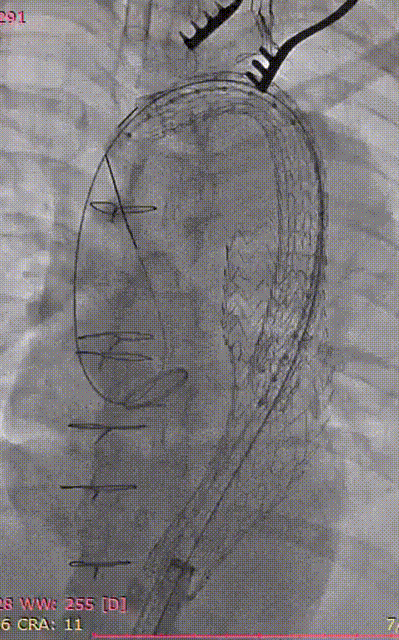

3. 交换lunderquist超硬导丝,置入DSF2265导引鞘,沿导引鞘先置入GORE® TAG® 胸主动脉覆膜支架系统 TGU313115,造影确认支架位置并释放。

gore医疗怎么样「胸有乾坤」可调可控 精准出击——四川大学华西医院肖正华教授团队:CADS治疗B型主动脉夹层病例分享_https://www.jmylbn.com_新闻资讯_第21张

释放远端CTAG

4. 继续送入近端GORE® TAG® 可主动调控胸主动脉覆膜支架TGMR313120,顶住导丝以左颈总后缘定位。

gore医疗怎么样「胸有乾坤」可调可控 精准出击——四川大学华西医院肖正华教授团队:CADS治疗B型主动脉夹层病例分享_https://www.jmylbn.com_新闻资讯_第22张

CADS支架定位

gore医疗怎么样「胸有乾坤」可调可控 精准出击——四川大学华西医院肖正华教授团队:CADS治疗B型主动脉夹层病例分享_https://www.jmylbn.com_新闻资讯_第23张

CADS释放前回撤鞘

5. CADS第一阶段释放,支架从近端向远端打开,释放至50%直径。

gore医疗怎么样「胸有乾坤」可调可控 精准出击——四川大学华西医院肖正华教授团队:CADS治疗B型主动脉夹层病例分享_https://www.jmylbn.com_新闻资讯_第24张

6. 支架近端位置微调后,再次顶住导丝,二次释放。

gore医疗怎么样「胸有乾坤」可调可控 精准出击——四川大学华西医院肖正华教授团队:CADS治疗B型主动脉夹层病例分享_https://www.jmylbn.com_新闻资讯_第25张

术中小弯侧定位造影

gore医疗怎么样「胸有乾坤」可调可控 精准出击——四川大学华西医院肖正华教授团队:CADS治疗B型主动脉夹层病例分享_https://www.jmylbn.com_新闻资讯_第26张

CADS释放一半后近端位置调整

7. CADS第二阶段释放,继续将超硬导丝顶紧大弯侧,释放CADS支架,支架由远端向近端打开至全直径,锁线钢丝全程将支架与输送系统进行固定,支架释放过程无移位,释放后,支架小弯侧贴附良好,无“鸟嘴”;最终造影可见隔绝良好,无内漏。

gore医疗怎么样「胸有乾坤」可调可控 精准出击——四川大学华西医院肖正华教授团队:CADS治疗B型主动脉夹层病例分享_https://www.jmylbn.com_新闻资讯_第27张

CADS第二阶段释放

gore医疗怎么样「胸有乾坤」可调可控 精准出击——四川大学华西医院肖正华教授团队:CADS治疗B型主动脉夹层病例分享_https://www.jmylbn.com_新闻资讯_第28张

CADS完全释放后造影